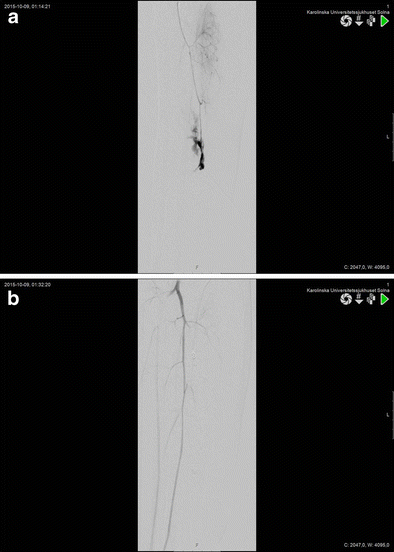

Extravasation posterior tibial artery after gunshot trauma to the lower extremity. Angioembolization of tibial posterior artery was performed